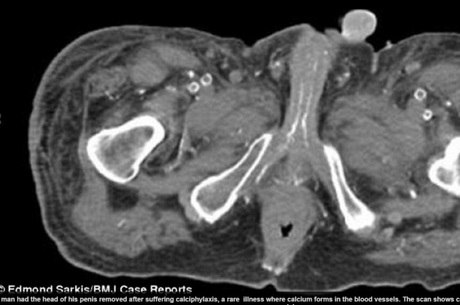

Homem perde parte de órgão sexual doença no sangue

Reprodução/DailyMail: Problema de circulação fez com que

pele apodrecesse e parte do órgão teve de ser retirada

A cirurgia levou quatro horas e homem de 54 anos morreu com infecção

Um homem de 54 anos teve parte de seu órgão sexual retirada após descobrir um raro tipo de doença no sangue. Em partes específicas do corpo como o pênis, pernas e nádegas, sua pele escureceu e teve de ser retirada. A dor era tanta que nem os medicamentos conseguiam melhorar a situação. As informações são do site DailyMail.

O médico Edmond Sarkis, que tratou o senhor no Centro Médico de Nova Jersey, nos Estados Unidos, afirma que o diagnóstico foi de necrose, onde a pele morre prematuramente e “apodrece”.

— Assim que olhamos para as feridas já sabíamos o que estava acontecendo. Elas estavam com cor roxa muito escura, quase pretas. Nunca vi algo tão forte assim. Estava tomando todo o corpo dele.

Após exames, os médicos perceberam que o homem sofria de doença rara onde cálcio se acumula nas veias dos tecidos da pele. Sarkis afirma que os problemas de rim que o homem também tinha poderiam agravar a situação.

— Como os órgãos param de filtrar as toxinas do sangue, o cálcio acaba se acumulando. Por isso as manchas escuras e a dor excessiva, porque o sangue começa a ter dificuldades para passar.

Depois do diagnóstico, os médicos levaram o senhor à sala de operação, e a cirurgia para remover parte do órgão sexual que havia escurecido levou quatro horas. Após ter se recuperado, o homem voltou para casa, mas faleceu depois de contrair uma infecção, pois estava debilitado e pegou uma pneumonia.